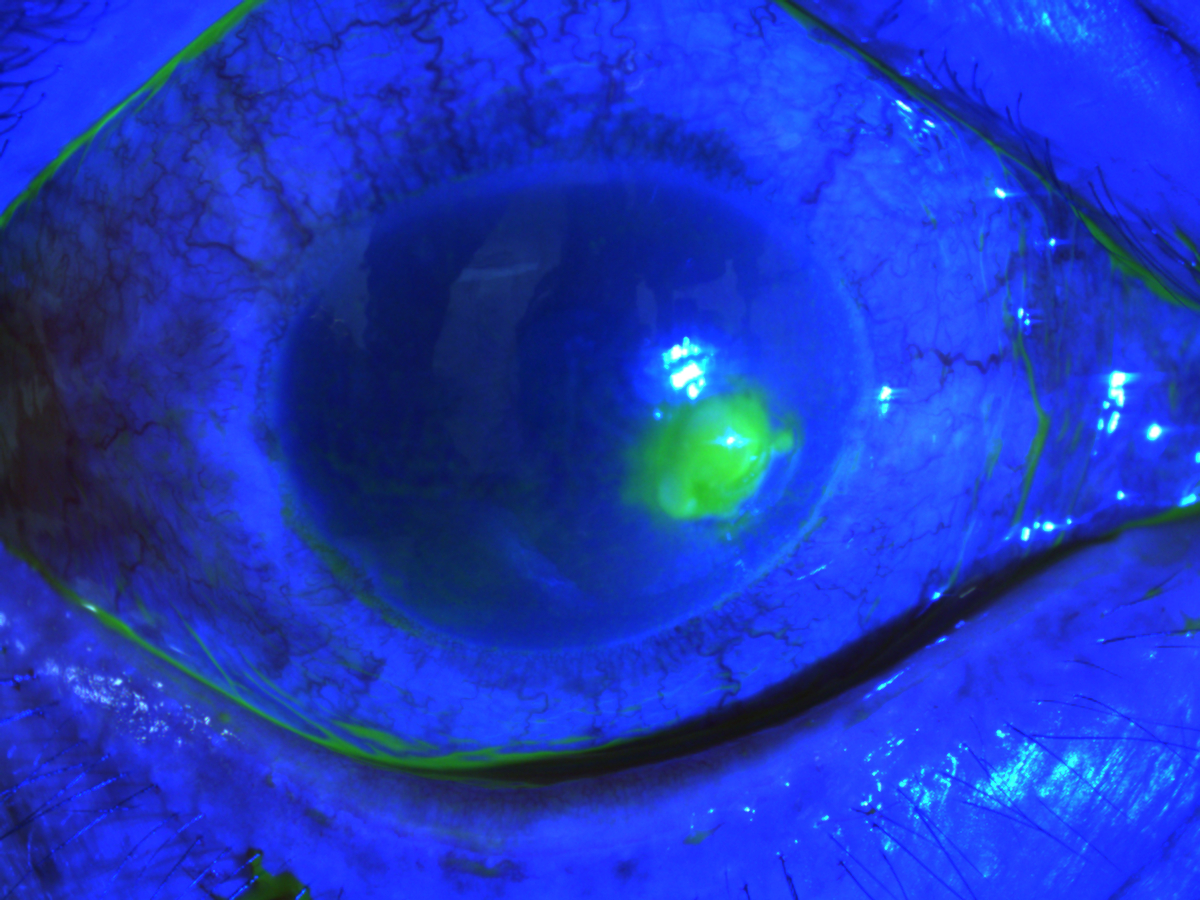

Qua thăm khám, bác sĩ phát hiện bệnh nhân mi sưng nề, kết mạc cương tụ toàn bộ, ổ loét giác mạc 5-7 mm, đáy bẩn bờ không đều, giác mạc xung quanh phù, thị lực 1/10. Bệnh nhân được làm xét nghiệm nhuộm soi vi khuẩn, nấm chất nạo ổ loét, kết quả tụ cầu dương tính, chẩn đoán mắt phải viêm loét giác mạc do vi khuẩn. Ngay sau đó, bệnh nhân được điều trị tích cực bằng thuốc kết hợp dinh dưỡng giác mạc, liệt điều tiết. Sau 10 ngày điều trị, thị lực người bệnh đã cải thiện nhanh chóng, đạt 9/10.

- Tình trạng mắt phải bệnh nhân khi vào viện